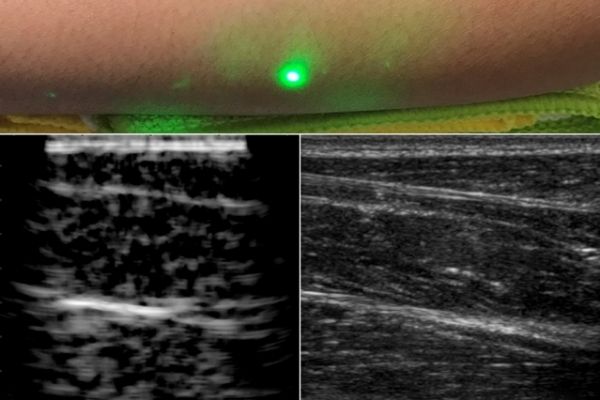

Image: A new ultrasound technique uses lasers to produce images beneath the skin, without making contact with the skin as conventional ultrasound probes do. The new laser ultrasound technique was used to produce an image (left) of a human forearm (above), which was also imaged using conventional ultrasound (right). Image courtesy of the researchers